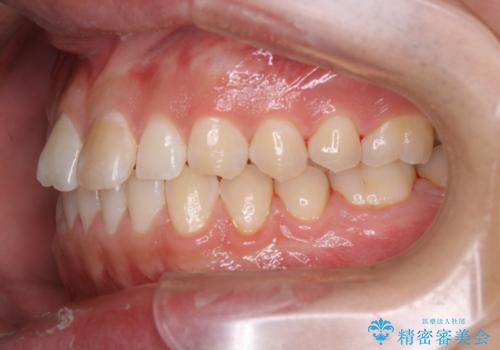

- 矯正治療を考えていて、歯科医院が久しぶりのためまずはクリーニングしたいとのことでした。PMTC60分コースを行いました。

- 歯を白くする目的の施術ではありません